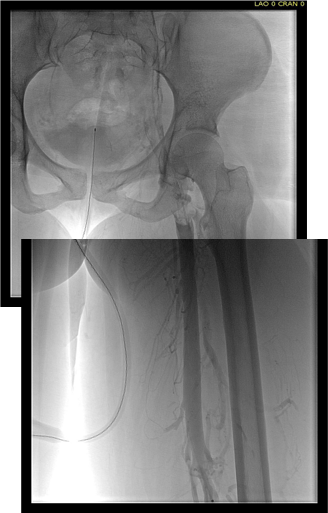

Examination revealed a fit and trim man in his 70’s in no apparent distress. He had bilateral leg edema that was moderate with small superficial and tender ulcers of the right posterior distal calf. Pulses were normal. He was taken to our hybrid suite and venography from femoral vein access in the proximal thigh in the supine position revealed his right and left iliac venous systems to be occluded (below figures).

Wire access into the iliac systems was performed with Glidewire and Glidecatheter periodic venography to confirm that I had not exited the vein. Unlike the arterial system, extravasation from being extravenous does not have the consequence of bleeding, hematoma development, and pseudoaneurysm formation because of the low pressure, but it can be a long procedure and uncomfortable as well so these are done under general anesthesia.

Once position confirmed to be in the iliac vein, the vein was dilated to allow for greater ease of movement. In the case of the uncrossable filter, I switched to access from above via a right internal jugular vein access.

Once the wire crossed into the iliac vein from above, it was captured and brought out. While ballooning by itself is inadequate for revascularization, it greatly eases wire capture and on the right, it was done simply by driving the wire from above into the sheath. Wire capture wins access across the iliocaval and IVC filter occlusion from below.